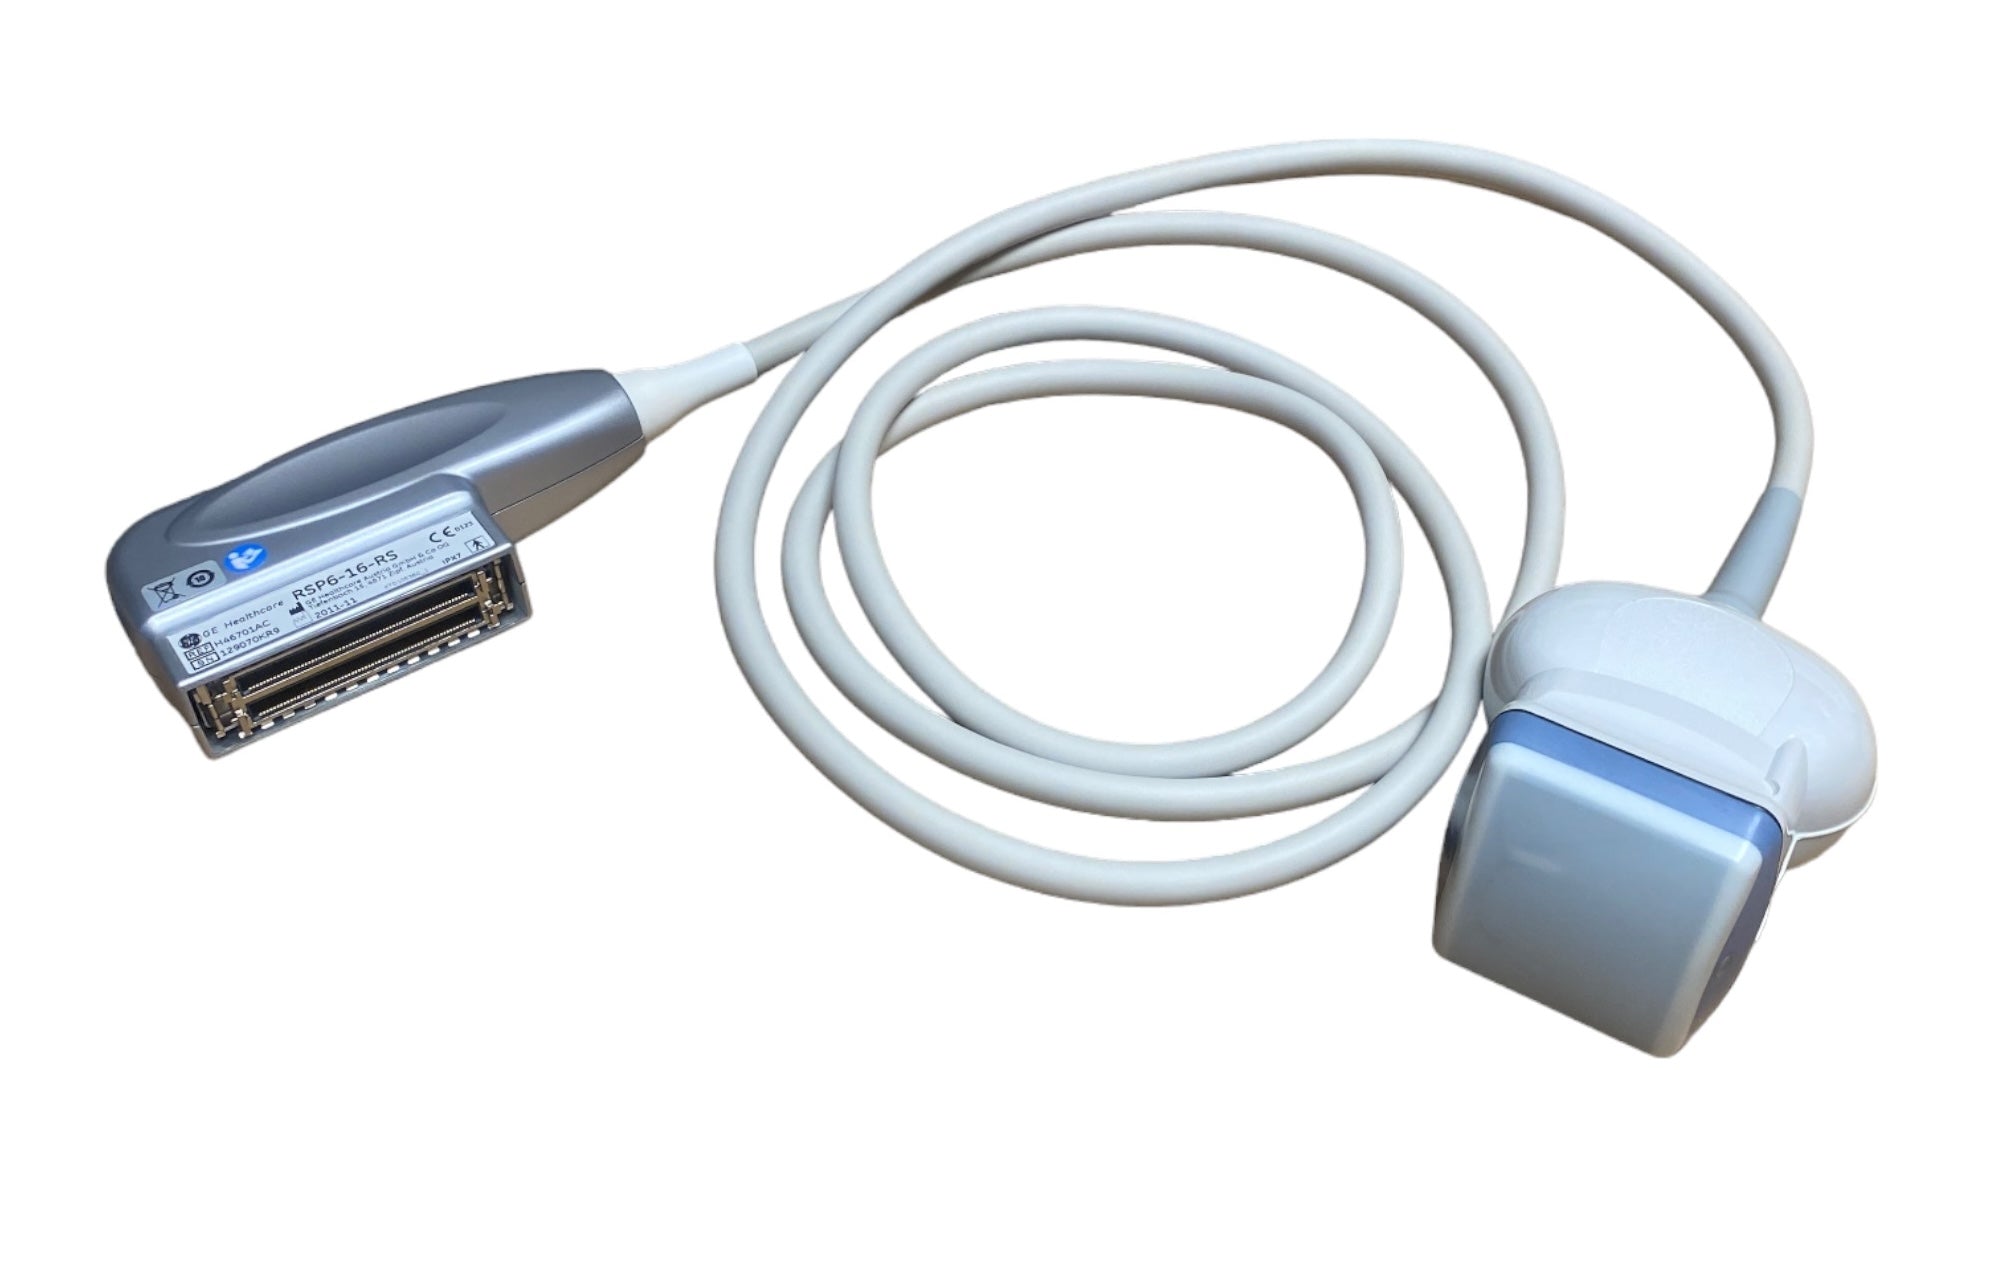

DIAGNOSTIC ULTRASOUND MACHINES FOR SALE

GE RSP6-16-RS Ultrasound Volumetric Probe 2011

Sale price$ 6,690.08